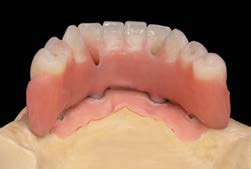

Các Implant ngắn 6.5mm BTI được đặt bằng cách sử dụng quy trình khoan định hướng sinh học (biologically guided drilling protocol) độc quyền của BTI, với lực vặn chèn được đo tại thời điểm đặt để xác nhận sự phù hợp cho việc chịu lực tức thì. Các phục hình tạm thời liên kết bắt vít được gắn ngay sau phẫu thuật để ổn định sự phân bố lực trong quá trình tích hợp xương. Từ 3 đến 6 tháng sau, chúng sẽ được thay thế bằng các cầu răng sứ kim loại cố định hoặc phục hình lai kim loại-nhựa, đảm bảo phục hình hoàn hảo cho bệnh nhân tiêu xương dọc.

Thành công vượt trội này đến từ hai yếu tố chính. Đầu tiên là quy trình khoan định hướng sinh học của BTI nhằm bảo tồn tối ưu kết cấu vi mô của phần xương xương ổ răng và đạt được độ ổn định vững chắc ban đầu – điều thiết yếu cho bệnh nhân tiêu xương dọc. Thứ hai, sự tuân thủ nhất quán sử dụng phục hình liên kết (splinted prostheses) đã giúp phân tán lực nhai hiệu quả, giảm stress cục bộ lên từng Implant ngắn 6.5mm BTI riêng lẻ và hạn chế đáng kể các vi dịch chuyển trong chu trình lành thương.

Trong suốt 8 năm theo dõi, hệ thống Implant ngắn 6.5mm BTI được triển khai với kỹ thuật phẫu thuật sinh học và tải lực tức thì đã đưa ra những báo cáo hiệu suất lâm sàng, quang tuyến cực kì khả quan. Sự vắng bóng hoàn toàn của các ca thất bại, tỷ lệ tiêu xương viền cổ cực thấp, cùng với việc không có biến chứng lớn phục hình là những bảo chứng mạnh mẽ rằng: Implant ngắn 6.5mm BTI là giải pháp ưu việt và hoàn toàn khả thi để vượt qua mọi thách thức của tình trạng tiêu xương dọc mà không cần sử dụng đến các thủ thuật ghép xương phức tạp, kéo dài thời gian điều trị.